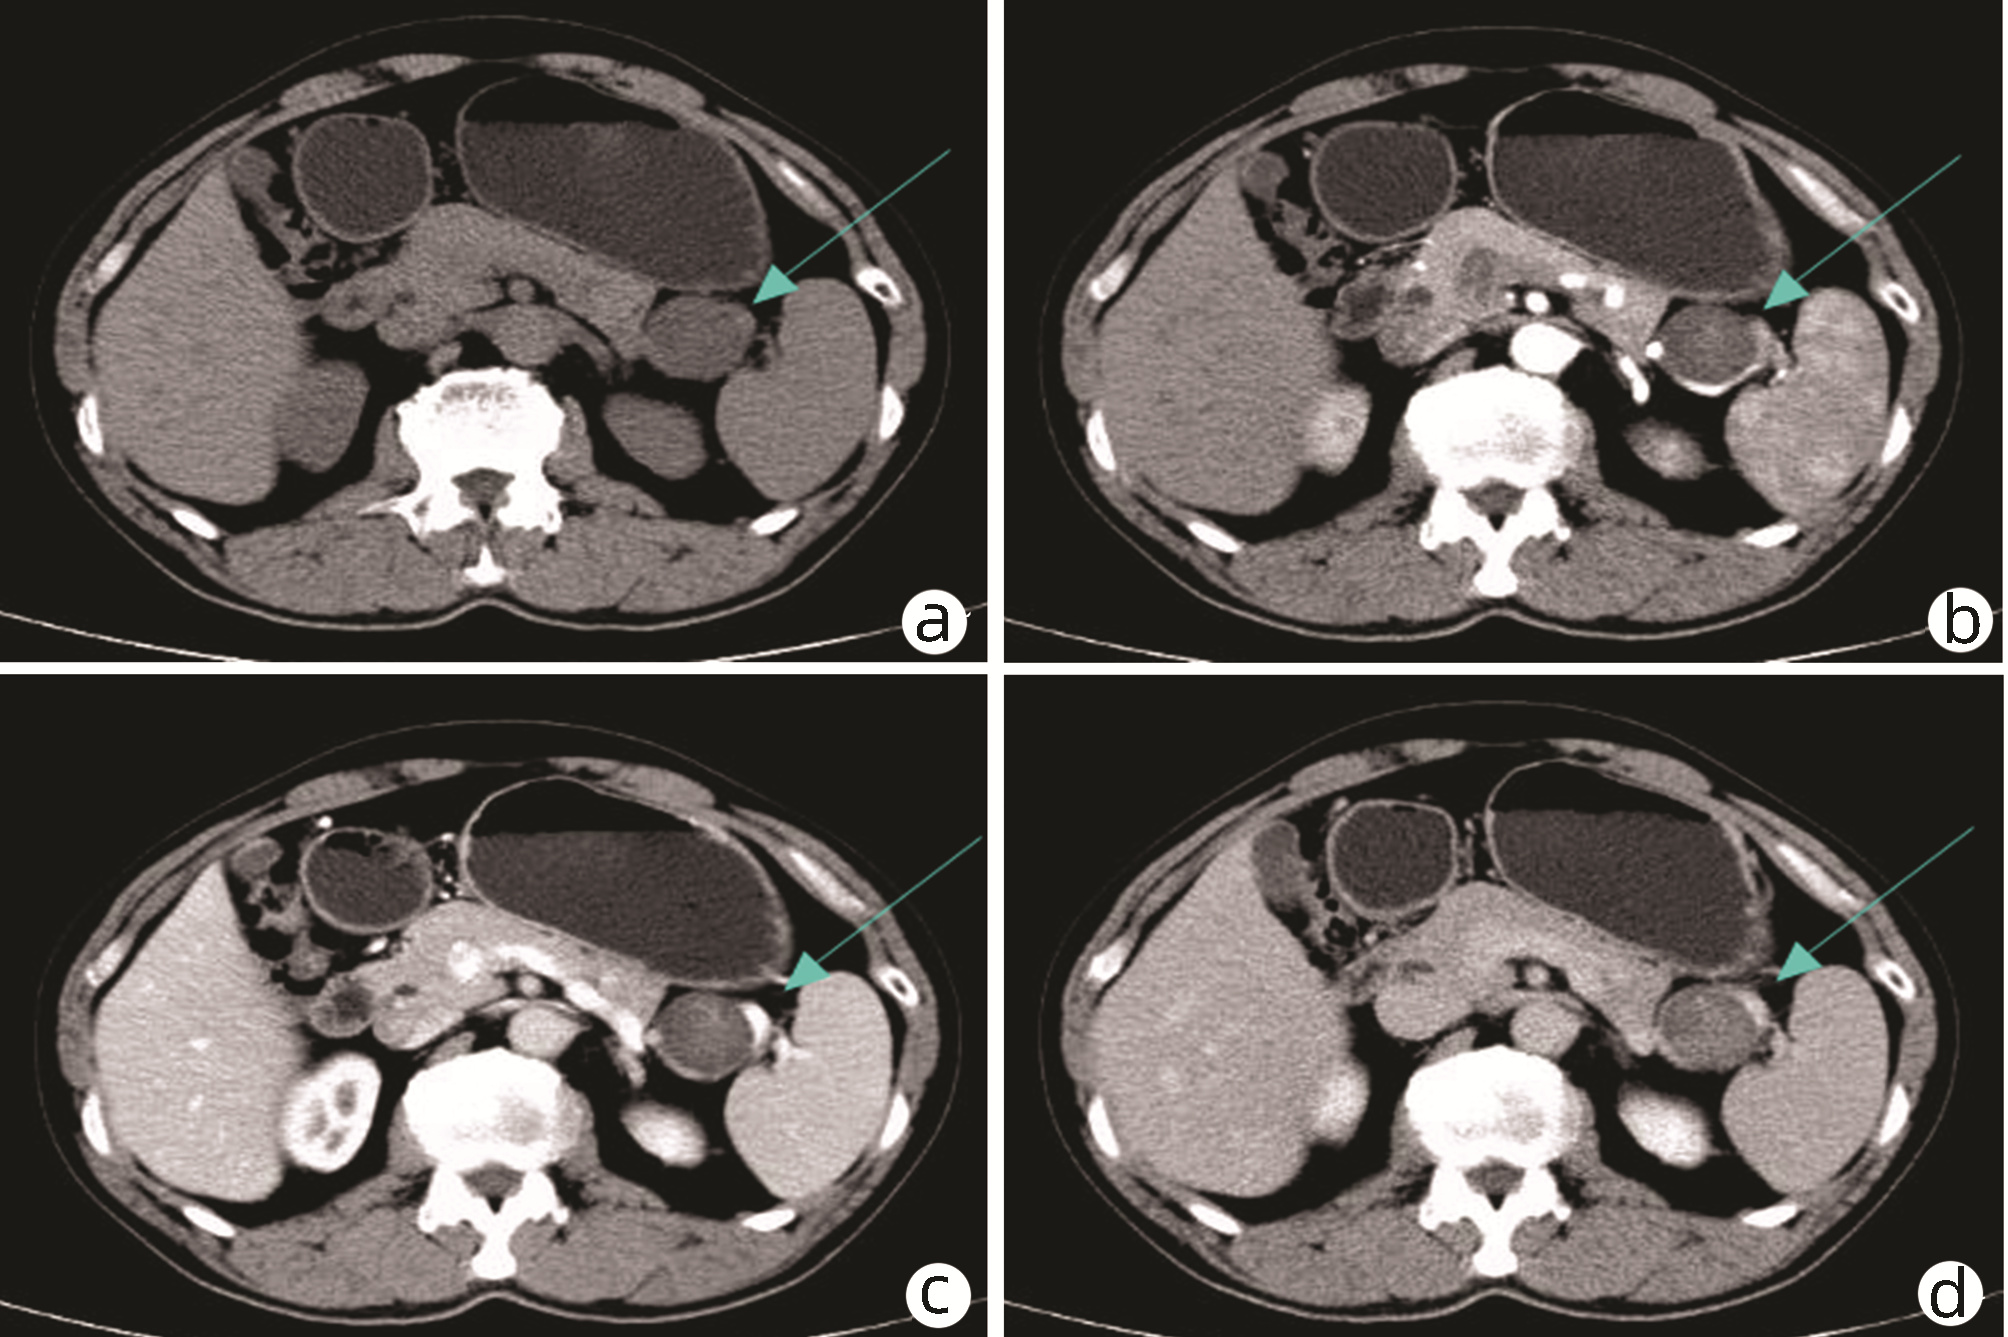

目的  通过回顾性分析肿瘤相关性急性胰腺炎(AP)患者的临床资料,评估胆胰及壶腹部肿瘤与AP发病之间的关系,探讨肿瘤相关性AP的临床特点。  方法  收集2013年1月—2021年8月郑州大学第一附属医院收治的AP患者病例资料。分析AP病因构成及肿瘤相关AP的发病率变化;对比分析肿瘤及非肿瘤AP,以及不同肿瘤部位AP的临床特征差异,探讨肿瘤相关AP的发病特点。正态分布的计量资料两组间比较采用t检验,多组间比较采用单因素方差分析,进一步两两比较采用SNK-q检验;非正态分布的计量资料两组间比较采用Mann-Whitney U检验,多组间比较采用Kruskal-Wallis H检验,进一步两两比较采用Wilcoxon秩和检验;计数资料二分类组间采用χ2检验或Fisher’s精确检验法比较,多分类组间比较采用拟合优度检验。应用受试者工作特征曲线(ROC曲线)评估胰腺肿瘤相关AP的鉴别因素;采用logistic多因素回归分析肿瘤相关性AP的独立影响因素。  结果  共入组AP患者8106例,肿瘤相关性AP患者84例,占1.04%。84例肿瘤相关AP患者平均年龄显著大于非肿瘤组(t=6.050, P<0.001)。初发AP至确诊肿瘤平均时间为7.38个月;轻症急性胰腺炎(MAP)75例(89.2%),中度重症急性胰腺炎(MSAP)8例(9.5%), 重症急性胰腺炎(SAP)1例(1.2%)。肿瘤来源于胆道下段11例(13.1%),壶腹部13例(15.5%),胰腺60例(71.4%)。AP反复发作(RR=8.362, 95%CI: 3.162~22.115)、胰管扩张(RR=10.996, 95%CI: 3.871~31.236)、胆管扩张(RR=7.738, 95%CI: 2.521~23.752) 和白细胞计数(RR=0.766, 95%CI: 0.666~0.881)是肿瘤相关性AP的独立影响因素(P值均<0.001)。  结论  肿瘤相关AP以中老年男性多发,临床多表现为MAP、易反复,多伴胰胆管扩张,肿瘤标志物CA19-9持续性升高等。具有上述特征且无明显诱因的AP需完善胆胰及壶腹部的影像学精查,并加强随访,避免肿瘤漏诊影响预后。